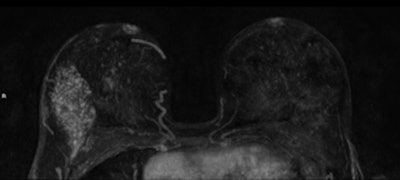

A 45-year-old woman with invasive lobular carcinoma (ILC) in her right breast shown as heterogeneous segmental nonmass enhancement of 75 mm on preoperative breast MRI (axial and sagittal maximum intensity projection). The ILC was mammographic occult and only 8 mm on ultrasound. After pathological proof of the more extensive size, the treatment was altered to mastectomy. All images courtesy of Kenneth Pengel and Dr. Claudette Loo.